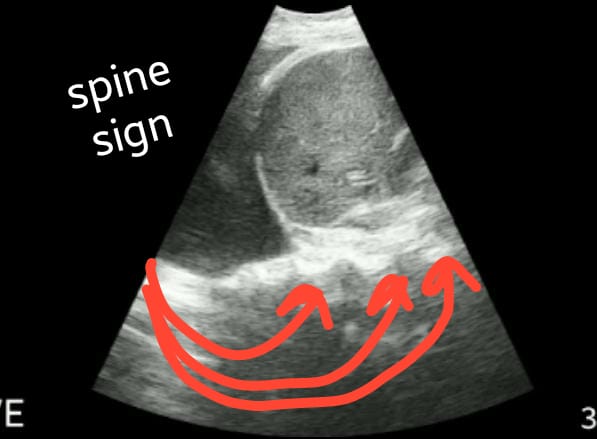

Na imagem acima podemos ver o parenquima hepático a direita da tela , separado do derrame pleural ( região anecoica) a esquerda da tela pelo diafragma( linha hiperecoica, linha branca, que circunda o figado). Na região inferior da tela, podemos ver o "spine sign", visualização dos corpos vertebrais abaixo do diafragma, na localização da coluna torácica. No caso acima, o spine sign se prolonga além da linha do diafragma, pois o líquido, ou seja, o derrame pleural, permite sua visualização, permite a passagem do som. Se não houvesse líquido pleural, somente parenquima pulmonar, não seria possível essa imagem. Outras condições também permitem o surgimento dos corpos vertebrais além do diafragma, como: hemotorax, consolidações em pneumonias extensas, dentre outros.